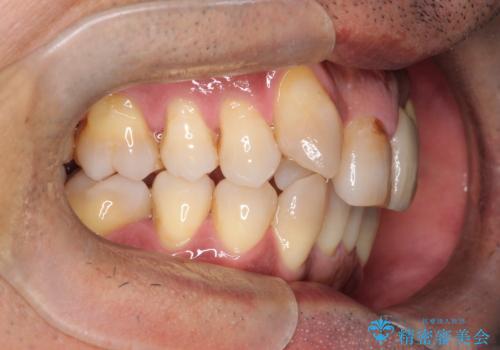

- 50代の患者様で、右上の八重歯と歯並びの乱れを気にされてご来院されました。特に、すでに装着されている前歯のセラミックブリッジを外したくないという強いご希望がありました。精密な検査の結果、八重歯を治すためのスペースが不足しているため、右上の4番目の歯(小臼歯)を抜歯し、そのスペースを利用して歯並び全体を整える治療計画を立案。装置には目立たないインビザラインを採用し、ブリッジを温存しながら八重歯の改善を目指しました。

今回の治療で最も重要だったのは、患者様のご要望通り既存のセラミックブリッジを外さずに矯正を進める点でした。計画通り右上の小臼歯を抜歯し、透明なインビザラインを使用して抜歯スペースを閉じながら、八重歯を正しい位置へ移動させました。ブリッジの形態と調和するに、他の歯の移動を工夫をすることで、複雑な条件をクリア。治療の結果、長年気にされていた八重歯が解消され、見た目が大きく改善しました。50代からでも、ご自身の要望を叶えながら、美しく機能的な歯並びを獲得していただけました。